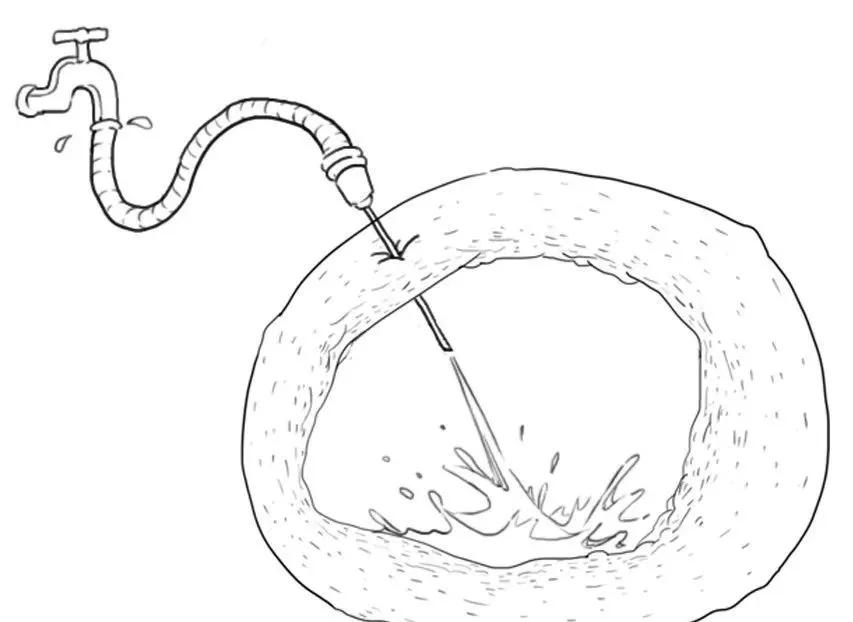

4、介入治疗:B超引导下巧囊穿刺,抽出囊液

这种方法较多用于复发的且有生育要求的年轻患者。或者用于较大的巧囊,抽吸囊液后配合药物治疗,以期在后面手术中缩小囊肿体积,减少术中卵巢皮质的丢失。

将它冲洗干净。